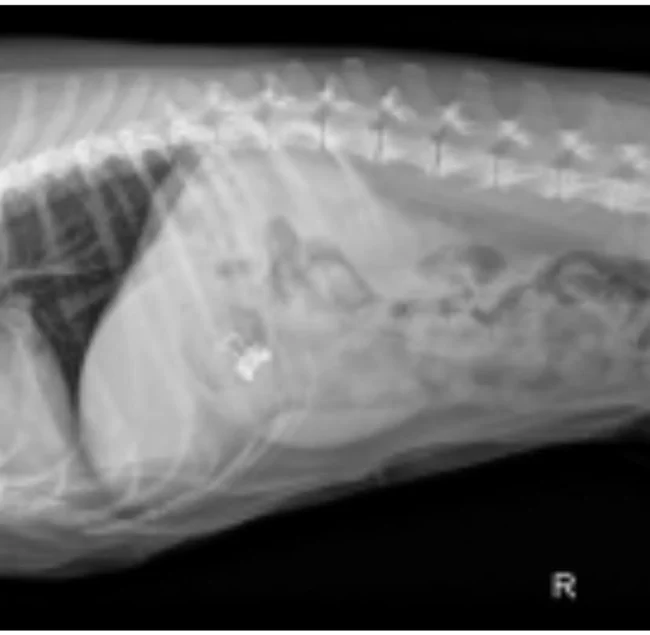

Снимок беременной собаки